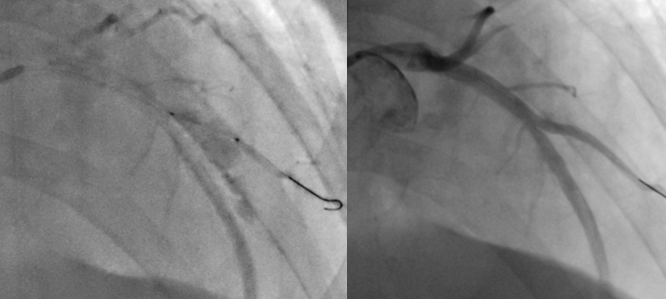

After diagnostic coronary angiogram, we proceeded to functional study of the D2 branch using 7Fr EBU 3.75 which confirmed functional significance with a RFR value of 0.75 and we proceeded with PCI. Ostium to proximal D2was pre-dilated with non-compliant 2.0 & 2.5 as well as cutting 3.0 balloon with recoil noted on angiogram after balloon inflation.IVUS imaging revealed underlying heavily calcified lesion and a sized-down 3.0 Shockwave balloon was deployed hoping to crack the calcium.Unfortunately the situation was complicated by perforation at very proximal D2 after Shockwave balloon inflation. The leak was localized at D2, yet balloon tamponade failed to seal the leak and hence 3.0 cover stent was deployed at D2 which seemingly sealed the leak.With a hope to reshape/align the carina, sequential dilatation of ostium D2 followed by kissing balloon inflation (KBI) with NC 3.5 in LAD & NC 3.0 in D2 was done. Unfortunately bleeding re-emerged after KBI, possibly due to crumpling of the proximal part of cover stent with possible extension of perforation into LAD. Thereafter the procedure became difficult as multiple balloon tamponade attempts in LAD/D2 failed to seal the leak. We ran out of options and had to deploy two cover stents in p-mLAD in order to control the leak. After stenting the LAD the leak improved but still some slow leak remained and we decided to go for reverse heparinization. Eventually the leak was much reduced to a minimal extent.